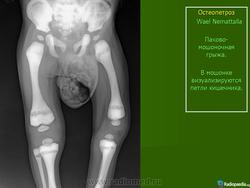

Морфологические изменения при остеопетрозе объясняются недостаточной активностью остеокластов. Макроскопически видно, что кости теряют костномозговой канал, концы длинных костей приобретают грушевидную форму (колбовидная деформация). Невральные отверстия становятся маленькими и сдавливают выходящие нервы. Первичная спонгиоза, которая удаляется в ходе начального роста, остается и заполняет полость костномозгового канала. Она не оставляет места для кроветворной части костного мозга и препятствует формированию зрелых костных балок. Формирующаяся кость не восстанавливает естественные структуры и имеет тенденцию к сохранению в грубоволокнистом состоянии. В конечном итоге эти внутренние аномалии делают кость хрупкой. Гистологически существенных изменений в количестве остеокластов обнаружить не удается, их число может быть чуть увеличенным, нормальным или уменьшенным.

Мраморная болезнь (болезнь Альберс-Шенберга) - семейный генерализованный остеосклероз, протекающий с лейкемической реакцией крови у детей, с анемией и лейкопенией у взрослых, нередко с атрофией зрительных нервов и глухотой. Характерны деформация мозгового и лицевого черепа, заращение придаточных полостей носа плотной бесструктурной костной тканью. Ввиду постепенного сужения отверстий в черепе и межпозвонковых отверстий могут возникать полиморфные проявления поражения периферической нервной системы как на черепном, так и на позвоночном уровнях. В позвонках костные балки губчатого вещества утолщены и уплотнены. В трубчатых костях отмечается сужение, а затем и исчезновение костномозговых полостей, эпифизы булавовидно утолщены и поперечно исчерчены, имеется склонность к патологическим переломам. Наследуется по аутосомно-рецессивному типу и тогда, проявляясь в фенотипе в первые годы жизни, быстро приводит к смерти, или же - по аутосомно-доминантному типу, проявляясь в 20-40-летнем возрасте. Описал болезнь в 1907 г. Н.Е. Albers-Schonberg.